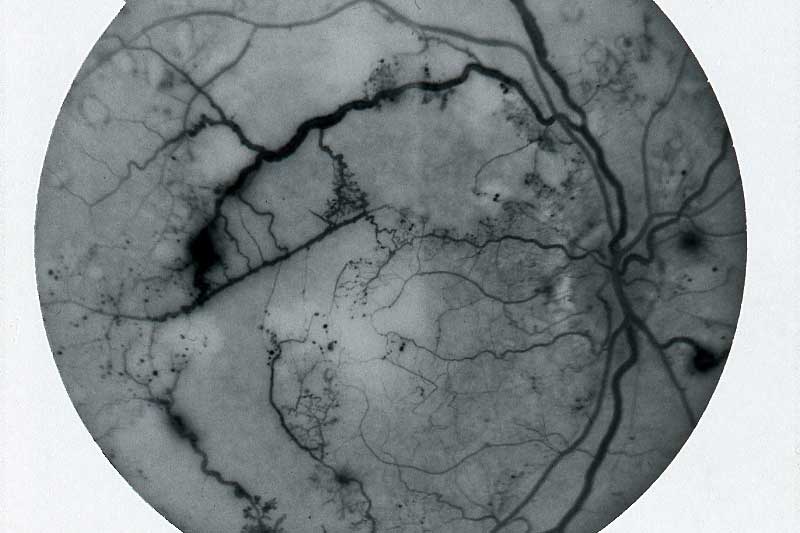

Technical Photography

A step beyond standard photography

Iris Imaging photographer has extensive medical and technical photography experience. A range of technical expertise that includes photographing the innermost layer of the cornea, macro focus stacking, and high-speed captures.